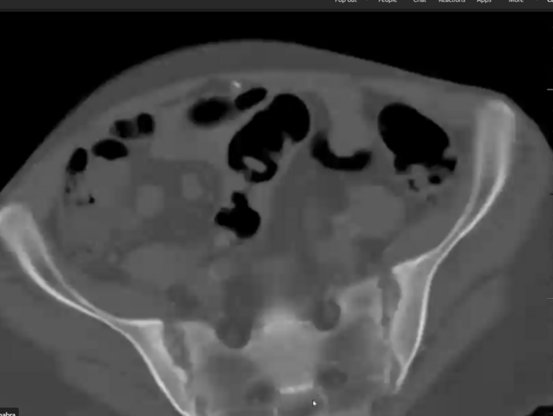

The pt has sarcoidosis w/ESRD; her SI joint erosions were related to hyperPTH @UTSWInternalMed@twitter.com

When there is bilateral sacroiliitis with erosions, DDx include:

1.hyperPTH in setting ESRD

2.ankylosing spondylitis

3.IBD

4.RA

In this case, look at the cortical resorption and the osteopenia in other areas. The pt has hyperPTH related to ESRD- Dr. Avneesh Chhabra